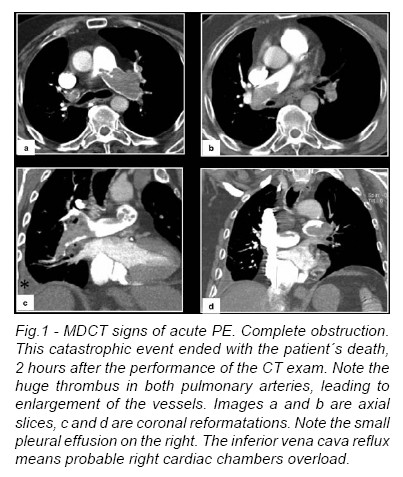

Complete Obstruction

On pulmonary angiograms,the diagnostic sign ofacute PE with complete obstruction is a concave filling defect or trailing edge that should be seen within the contrast material at thelevel of the obstruction.CTis able to show thrombus distal to the obstruction that cannot be seen on an angiogram. At the site of the thrombus, the diameter of the pulmonary artery may be increased because of impaction of the thrombus by pulsatile flow (Fig.1).